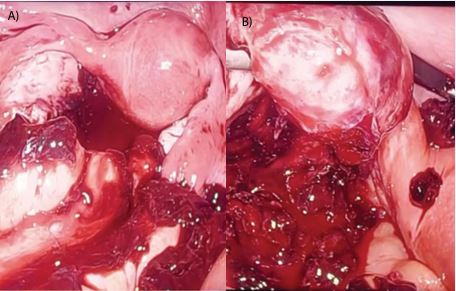

Initial laboratory workup demonstrated a hemoglobin level of 16.3 g/dL and a serum β-human chorionic gonadotropin (β-HCG) level of 3,300 mIU/mL. Although the elevated hemoglobin level was unexpected in the context of suspected intra-abdominal bleeding, possible explanations include hemoconcentration, individual variation, or technical factors, as it was not repeated. Subsequently, a transvaginal ultrasound was conducted, revealing a right adnexal mass measuring approximately 5 cm with heterogeneous echotexture, suggestive of an ectopic pregnancy. The endometrium appeared thickened, measuring 18 mm, with an empty uterus, no visible gestational sac. Given the clinical presentation, sonographic findings, and rising β-HCG levels without evidence of an intrauterine pregnancy, a decision was made to proceed with diagnostic laparoscopy. Intraoperatively, approximately 1 liter of hemoperitoneum was discovered, primarily in the pouch of Douglas. The uterus was confirmed to be non-communicating unicornuate, with a single right-sided uterine horn. The right ovary and fallopian tube were grossly normal. Interestingly, the left fallopian tube was completely absent, and a ruptured ectopic pregnancy was identified on the surface of the left ovary. No rudimentary uterine horn, fibrous band, or abnormal communication between the horn and the contralateral side was noted. The ectopic gestational tissue was excised from the ovarian surface using bipolar cautery, preserving the ovarian tissue and achieving complete hemostasis, Figure 1a & 1b. The specimen was retrieved using an endobag, and no intraoperative or postoperative transfusion was required.

Figure 1 a: Intraoperative image showing a unicornuate uterus with surrounding hemoperitoneum, indicating significant intra-abdominal bleeding.

Figure 1b: The left ovary demonstrating active hemorrhage at the site of rupture, consistent with an ovarian ectopic pregnancy.